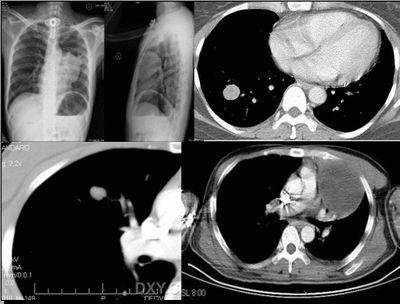

⑧患者,男,48岁,于2001年因“反复声嘶9个月”在外院确诊为喉鳞状上皮癌,行手术切除。10天前患者无明显诱因出现左侧背部疼痛,进行性加重,患者无咳嗽、咳痰、发热。

实验室检查:ce125:128uml ly:0. 6x109/l wbc:10.1x109/l ne:8.3x109/l

左上肺炎性假瘤:

细支气管上皮增生、纤维母细胞增生及纤维化,间质有炎细胞浸润及淋巴滤泡形成,边缘有坏死组织。